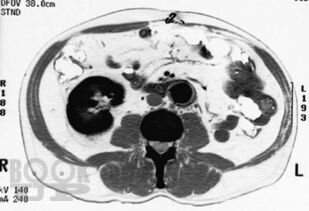

В атласе представлены более 1200 цветных иллюстраций по всем основным патологическим процессам, с которыми можно встретиться на практике, а также при изучении курса патологии или при подготовке к квалификационному экзамену по медицинским специальностям, проводимому в США (USMLE). Принцип построения атласа соответствует главам 7-го издания руководства «Основы патологии болезней Роббинса и Котрана» (Robbins and Cotran Pathologic Basis of Disease). Иллюстрации данного атласа дополняют рисунки, представленные в этом руководстве. В атлас включены иллюстрации наиболее важных рентгенологических изменений, которые отражают реальные клинические проявления при конкретных заболеваниях. Высококачественные иллюстрации имеют маркировку для определения ключевых признаков патологических изменений. В каждом наблюдении представлено комплексное описание ключевых морфологических признаков, а также клинико-лабораторные данные по наиболее важным разделам патологии. Картины макроскопических и микроскопических изменений дополнены цветными рисунками и схемами, а также соответствующими рентгенограммами. Атлас является прекрасным изданием, содержащим необходимый объём сведений или справочных материалов для читателя, имеющего различный уровень подготовки, — студента, врача, научного работника.